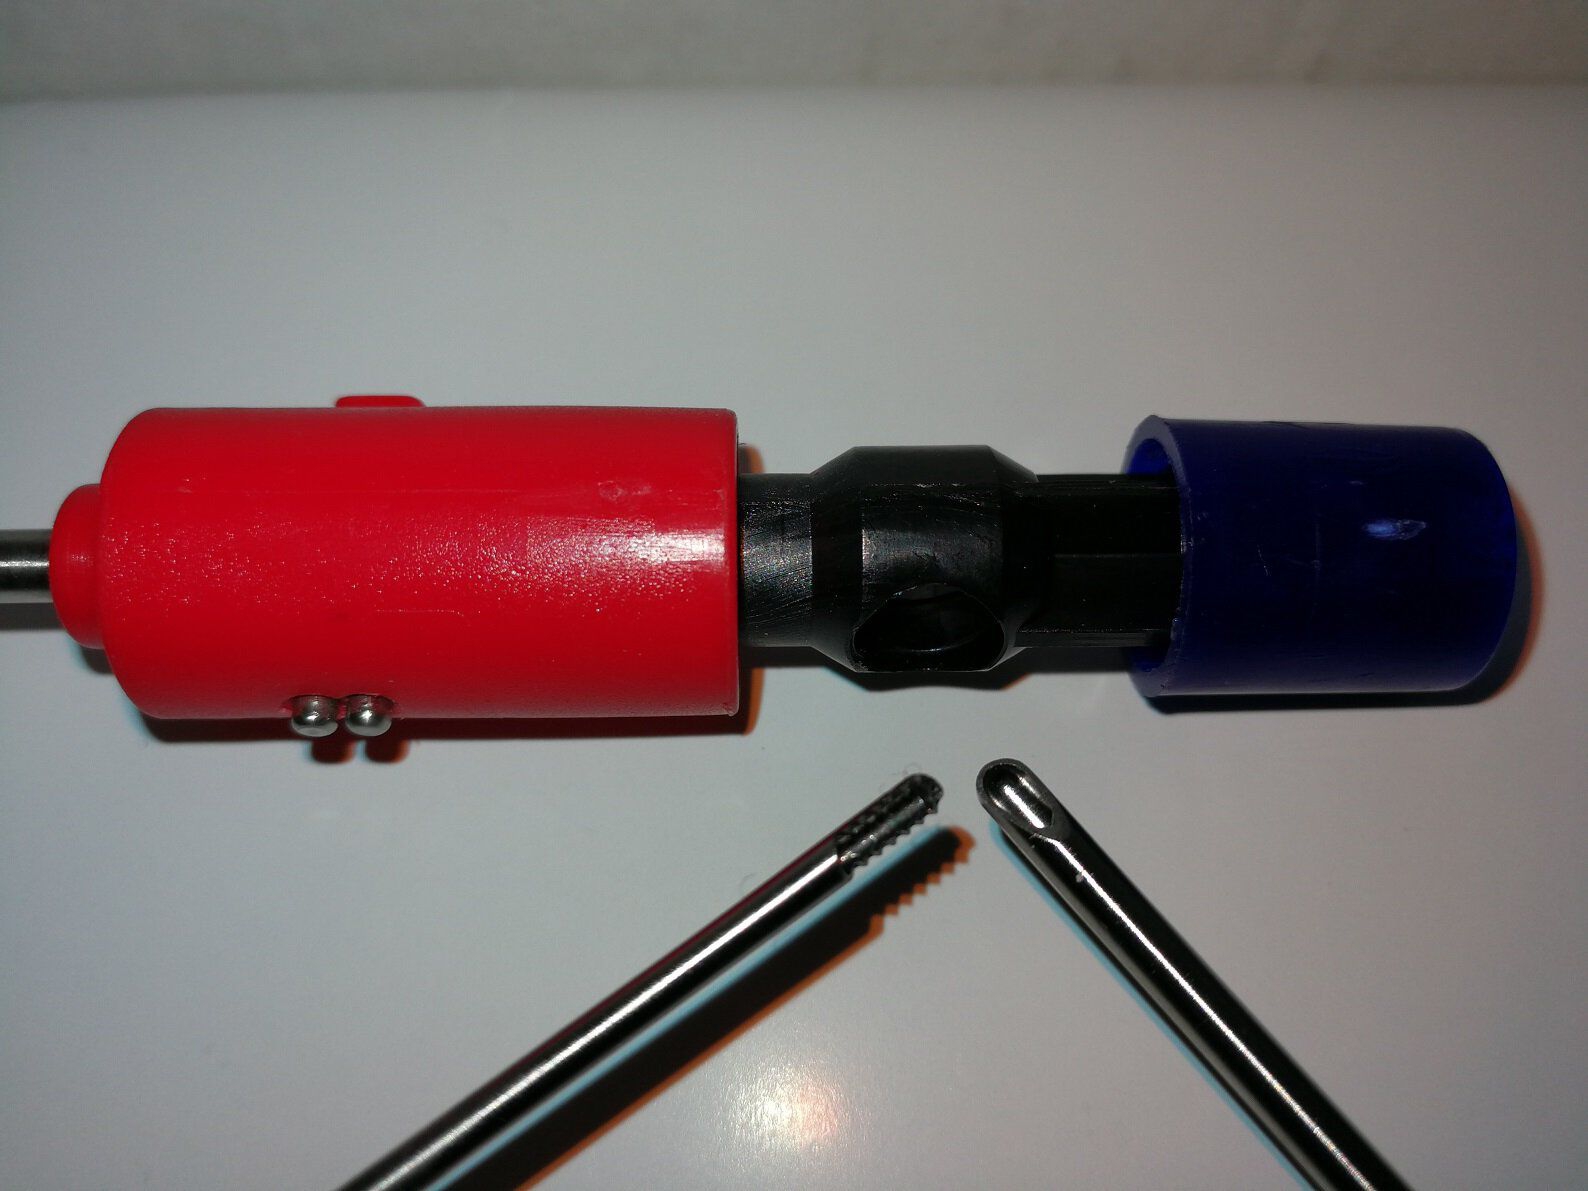

HB5616-02 ~ McKenty Septum-Elevator, 21,5cm ~

McKenty Septum-Elevator, 21,5cm